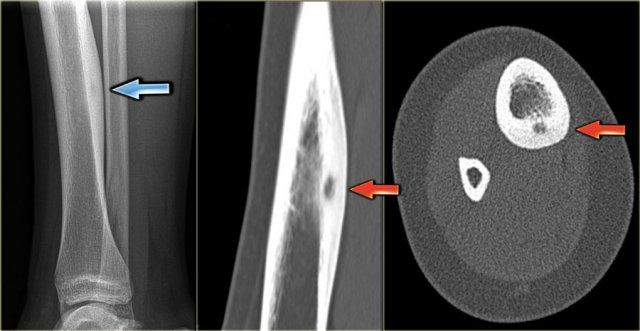

Ở đây, xơ cứng phản ứng là dấu hiệu rõ ràng nhất trên X-quang.

Có xơ cứng phản ứng với ổ tổn thương hầu như không nhìn thấy trên phim X-quang (mũi tên xanh), nhưng thấy rõ ràng trên CT (mũi tên đỏ).

Chụp CT thường rất hữu ích trong việc phát hiện ổ tổn thương trung tâm (nidus) và phân biệt u xương dạng xương (osteoid osteoma) với các tổn thương xơ cứng khác như u nguyên bào xương (osteoblastoma), viêm tủy xương (osteomyelitis), viêm khớp (arthritis), gãy xương do stress (stress fracture) và nội cốt (enostosis).